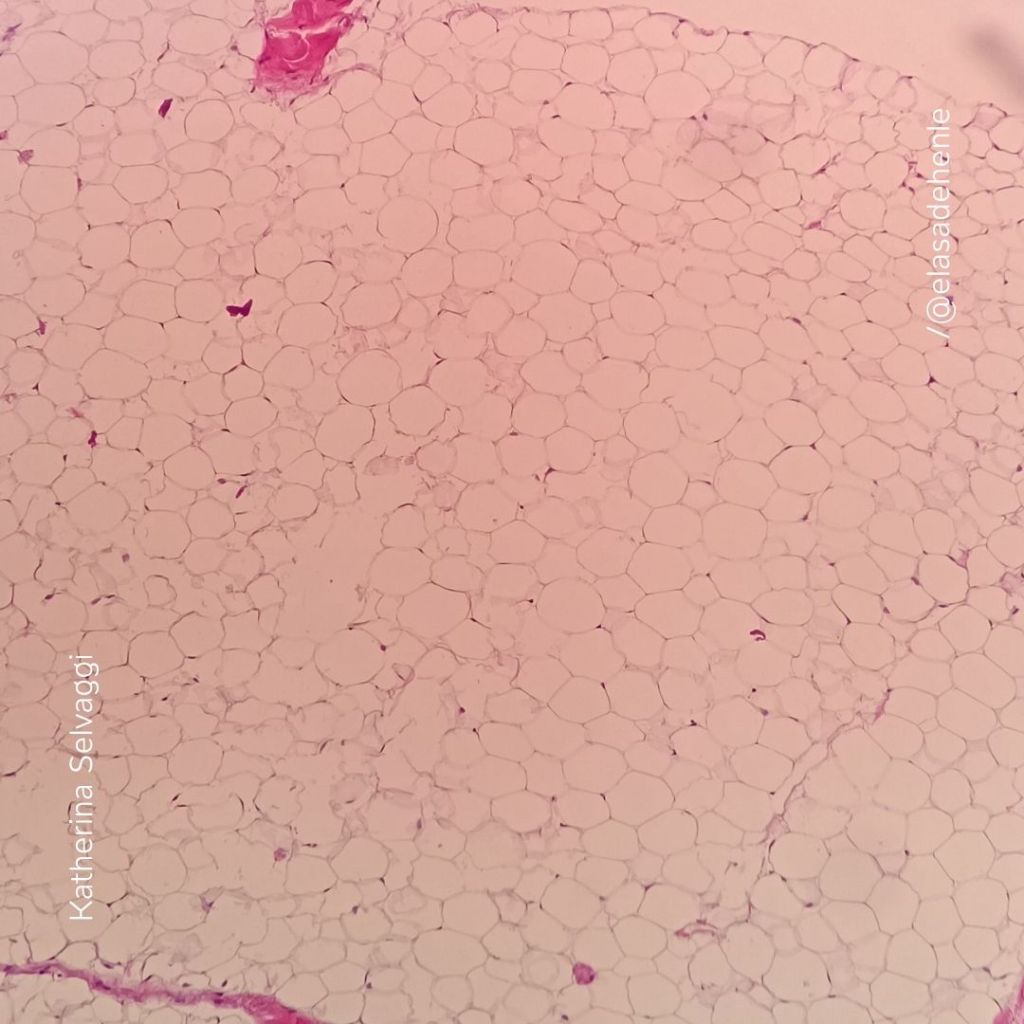

Hematoxilina y eosina

Lipoma

COMECA